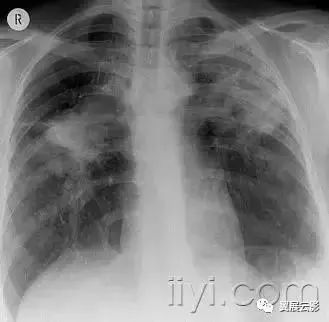

五十九、进展性大范围肺纤维化

病理:本病源自粉尘的慢性积聚和病人曝露于无机粉尘后的的胶原增生(主要见于煤炭工人)

平片和CT:呈肿块样病变,常为双侧性,发生于上叶(图56)。结节状的背景密度异常提示尘肺,伴或者不伴大范围纤维化邻近的气肿性破坏。与进展性大范围纤维化相似的病变,也可以见于结节病和滑石病。